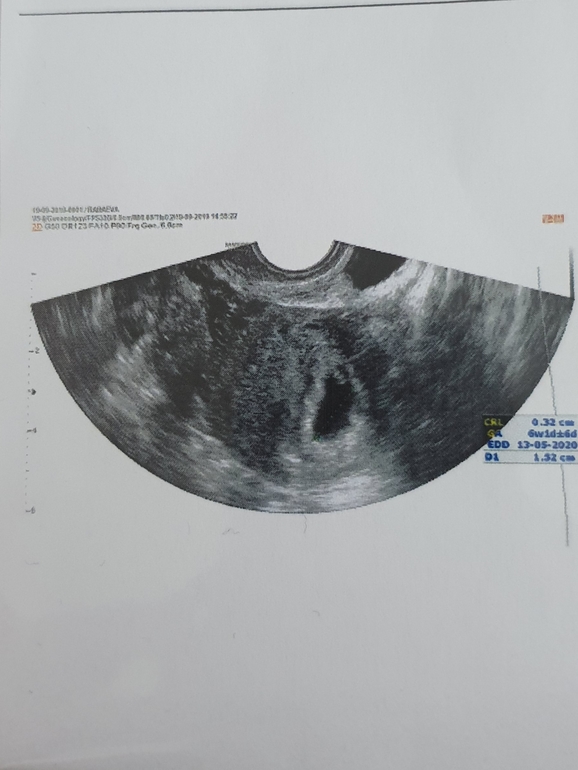

А вот и мы! 7 недель ровно.

Ну вот моя бусюлинка и показалась😍 Сердечко бьётся!❤

Г сказала, что мы на 6 дней моложе, но это нормально, так как О была на 20дц...посмотрела бьющееся сердечко, слушать пока не стали, сказала еще маленький, лучше не беспокоить!

Спасибо)) это второе, первое было в 5,5 еще не было видно эмбриона